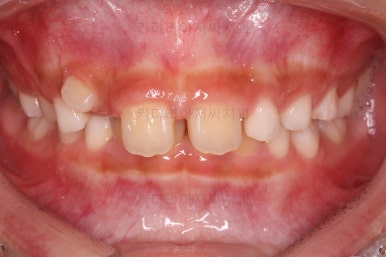

마찬가지로 초진시의 입안 모습입니다.

보호자분 말씀처럼 윗니가 아랫니에 비해서 나와보이는게 사실이네요.

그럼 정말 윗니가 튀어나온게 맞을까요?

이번 환자분은 무턱 + 돌출입 성장교정이 목표였지만 그전에 치아의 맹출경로가 엉켜서(화살표) 치아의 손상 혹은 매복치아의 우려가 있는 부분을 먼저 개선하기로 했습니다.